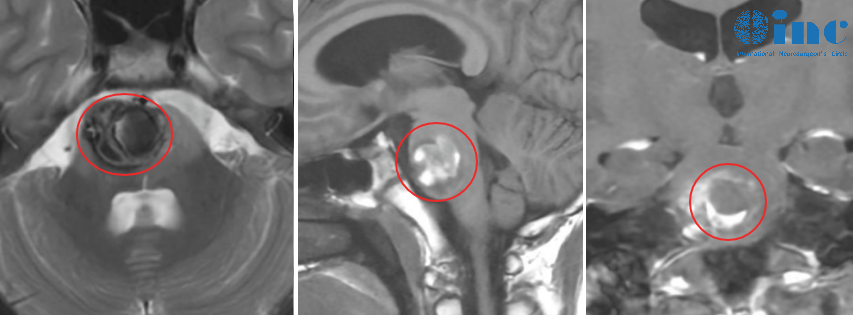

然而,3个月后的复查却险些将小雨一家拽回到曾经的噩梦中。复查报告上显示:脑干存在异常信号,考虑海绵状血管瘤;此外,核磁还发现了一个位于右侧天幕下的蛛网膜囊肿。寝食难安的父母赶紧联系了巴教授,没想到,巴教授却大笑说:别担心,这是好消息!

原来,报告上的“异常信号”并非当初残余的肿瘤,而是含铁血黄素的残留,这对于小雨当初如此巨大出血性的脑干病变来说是正常的,它并不是活跃性的海绵状血管瘤。

原来,由于脑干海绵状血管瘤极易反复、微量出血,当脑组织存在慢性出血或血管损伤时,其残留的代谢产物就会导致含铁血黄素沉积。当然这并非一种需要治疗的疾病,正如巴教授所说,这在小雨这样如此巨大的海绵状血管瘤全切术后是正常现象。